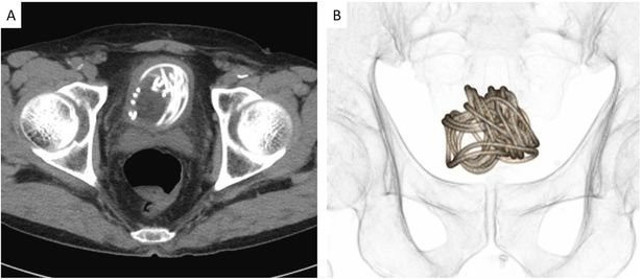

İpin ince olduğuna dikkat çeken doktorlar, ipin düğüm olması sebebiyle idrar torbasına bir delik açarak cerrahi bir müdahale gerçekleştirildiğini de duyurdu. Ameliyatın başarılı geçmesi için idrar torbasının 3-D modelinin yapıldığı ve bu sayede doktorların nasıl müdahale edeceklerinin anlaşıldığı açıklandı.

Tokyo’nun 160 kilometre uzağında yaşanan olay Urology Case Reports isimli tıp dergisinde yayınlandı. Araştırmayı kaleme alan ve operasyonda da yer alan Profesör Toshiki Kijima, “Tarama ve modelleme teknolojisi ameliyatın başarılı geçmesine katkı sağladı” dedi.